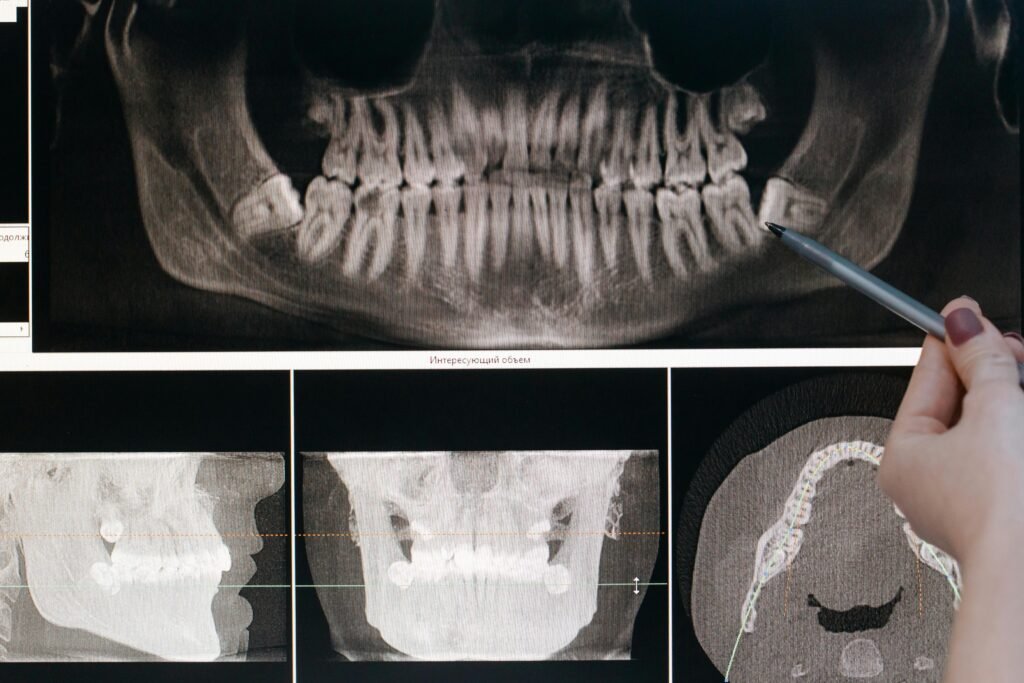

Minor oral surgeries are dental procedures performed to treat common oral health issues safely and effectively. These procedures may include tooth extractions, removal of impacted teeth, treatment of oral infections, or correction of minor jaw and gum problems. Performed under proper anesthesia, minor oral surgeries help relieve pain, prevent complications, and restore oral health.

Minor oral surgeries are essential when routine dental treatments are not sufficient to resolve certain conditions. They help maintain oral health, reduce discomfort, and ensure long-term dental stability with proper care.